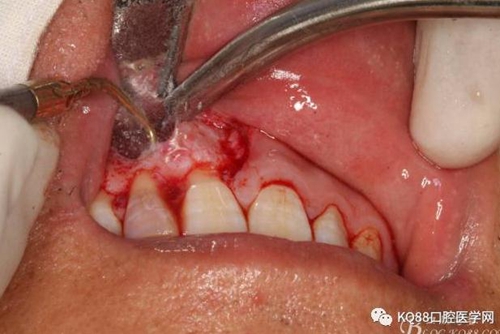

圖6.行唇側(cè)角形切口(11近中垂直切口+齦溝內(nèi)水平切口)垂直切口距離前庭溝約1~2mm。這樣可以減輕術(shù)后腫脹。

圖7. 角形切口中的齦溝內(nèi)切口情況:11號刀片伸進(jìn)齦溝內(nèi)斜切。